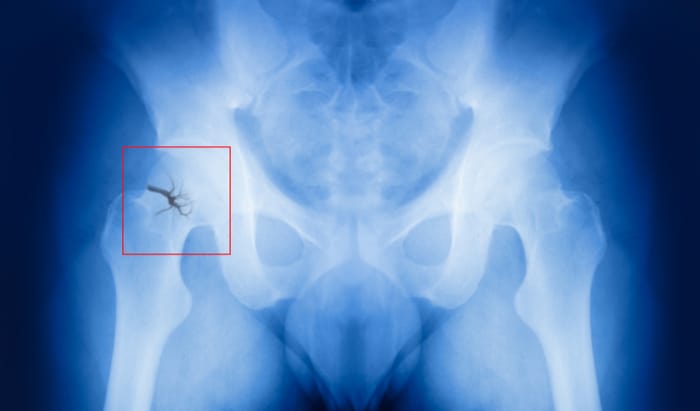

Clinicians use DEXA scans, which look at how porous or dense bones are, to assess the likelihood of fractures. DEXA scans detect bone weakness in osteoporosis, a condition that causes weakened bones, and to inform treatments, like prescribing the medicine bisphosphonate, to help prevent fractures in these people.

They used high energy intense beams of X-rays generated by Diamond Light Source, the UK’s national synchrotron, to examine bone flexibility at the nanoscale. They were able to assess how the collagen and minerals within bone flex and then break apart under load in the nanostructure of hip bone samples.

They compared the behaviour of the bone tissue samples under load between three groups of donors: those who had not suffered a hip fracture, or any other fracture; those without a bisphosphonate treatment history who had suffered a fractured hip; and those with a bisphosphonate treatment history who had suffered a fractured hip.